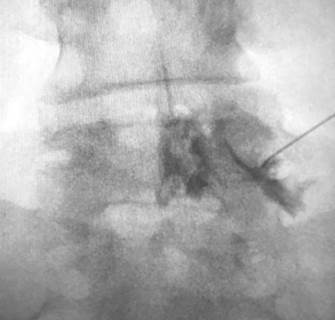

Al no responder al tratamiento instituido en base a tramadol y ketoprofeno, se le realizó una inyección peridural transforaminal de corticoides a nivel de los forámenes L4 y L5 derechos, (Figuras 1 y 2) según guía de la SIS (Spinal Injection Society). Previo control con 1 ml. de contraste iodado (iopamidol 300 mg/ml), se le administraron 20 mg de triamcinolona + 1 ml lidocaína 0.5% en cada foramen. Aproximadamente 6 horas después del procedimiento, instaló episodios de hipo de 8-10 por minuto, de 2 o 3 horas de duración, que se repitieron por un período de 50 horas, con interferencia en el descanso y en la alimentación. Los tradicionales tratamientos no farmacológicos tales como tragar agua fría, mantener la respiración, respirar en una bolsa, o la aplicación de masaje carotideo o presión supraorbital resultaron inefectivos, por lo que se le administró inicialmente 10 mg de domperidona intravenosa (iv) c/8 horas en las primeras 24 horas.